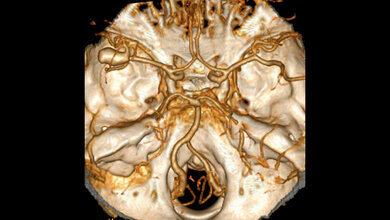

In einer neuen Studienarbeit haben Forscher/-innen der Universität Ulm und der Agaplesion Bethesda Klinik Ulm die Sterblichkeit von älteren Personen im Zusammenhang mit dem systolischen Blutdruck und dem Faktor „Gebrechlichkeit“ untersucht. Das Ergebnis: Das durch einen höheren systolischen Blutdruck bedingte Sterberisiko im Alter unterscheidet sich stark je nach der individuellen Fitness der Personen. Mit zunehmendem Lebensalter nimmt das Risiko für Bluthochdruck (Hypertonie) zu, da unter anderem die Gefäße an Elastizität verlieren. Mit dem Blutdruck steigt das Risiko für Herz-Kreislauf-Erkrankungen wie Schlaganfall oder Herzinfarkt. Deshalb zählt Hypertonie zu den großen vier Risikofaktoren.